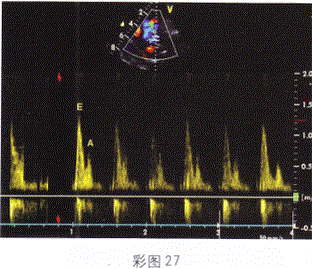

男性,66岁,胸闷、呼吸困难,心电图提示心肌梗死,超声检查二尖瓣舒张期血流频谱提示(彩图27)

- A.左心室顺应性减低

- B.左心室顺应性正常

- C.左心室舒张功能假性正常化

- D.室壁瘤形成

- E.二尖瓣狭窄

C

患者心电图提示心肌梗死,但频谱示E/A>1。